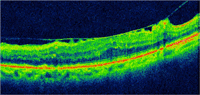

Mujer de 82 años con retinopatía diabética no proliferativa leve-moderada y sin edema macular clínicamente significativo (EMCS) en AO, con antecedentes de ambliopía en OD. Explicaba un control glicémico irregular. La paciente fue intervenida de catarata bajo anestesia tópica en AO con un intervalo de 6 meses entre cada ojo, sin incidencias operatorias. La AV tras la intervención de catarata fue de 0.5dif en OD y 0.25 dif en OI con corrección óptica. La paciente presentaba una retinopatía diabética no proliferativa (RDNP) leve-moderada desarrollando en el postoperatorio un leve edema macular (EM) en AO acompañado de metamorfopsia en OI, que requirió la realización de angiografía fluoresceínica (AGF) y tomografía de coherencia óptica (OCT) macular (

Figura 1 y

Figura 2 ).

Figura 2. OCT macular OI donde se aprecia con nitidez la tracción que la hialoides posterior ejerce sobre la retina interna